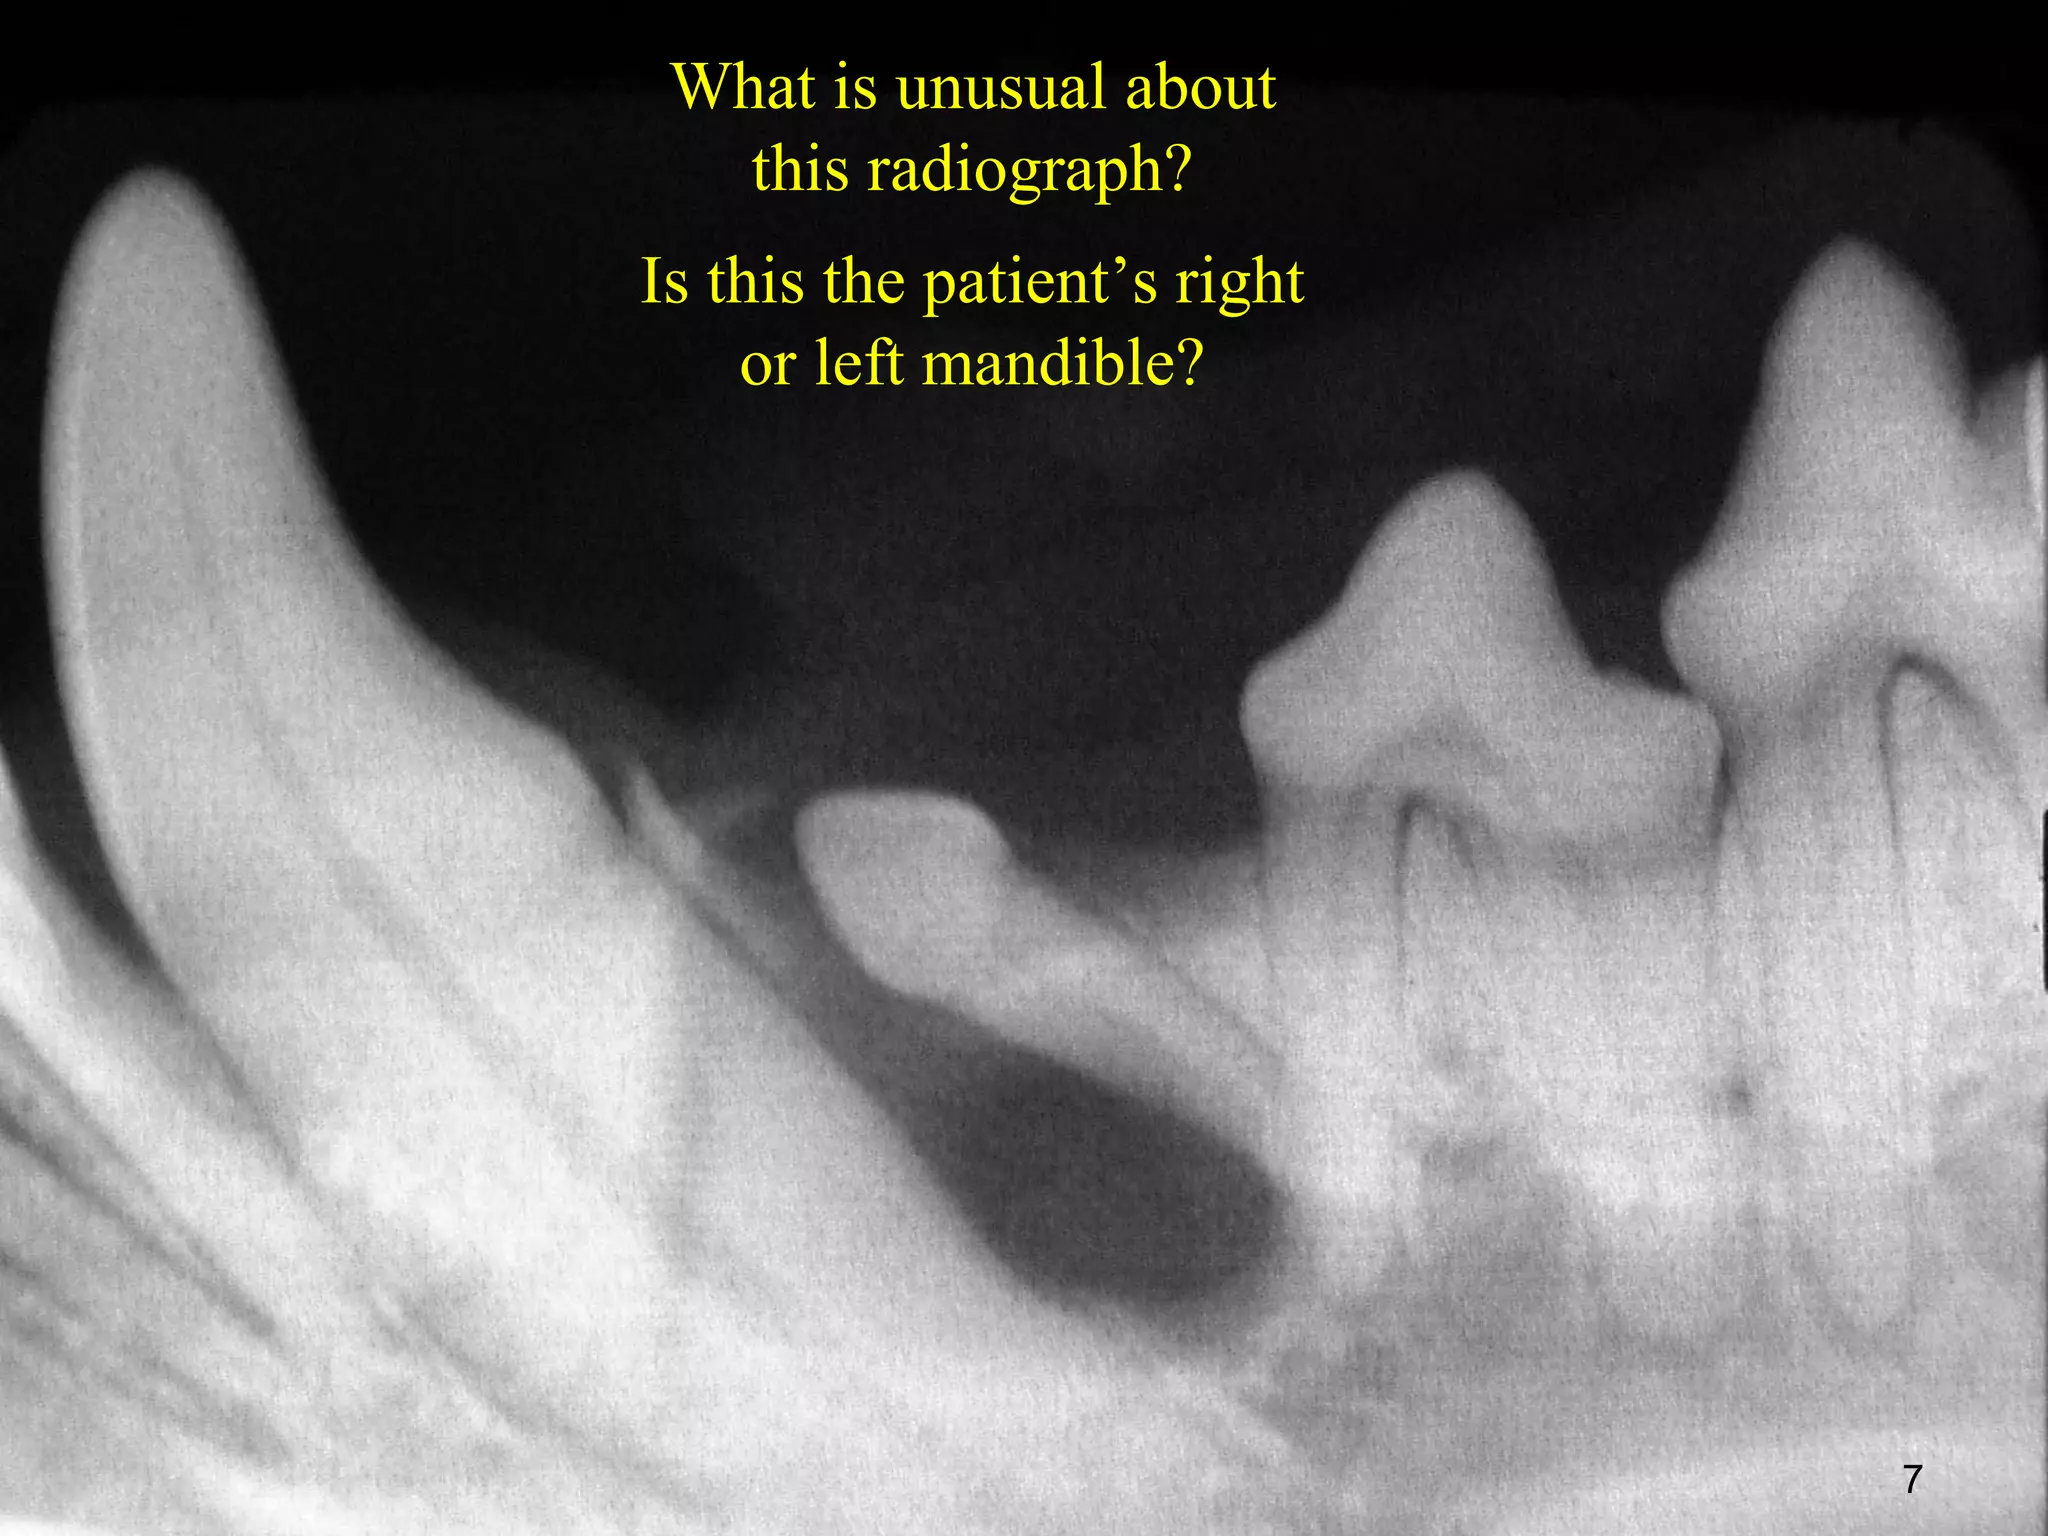

What is unusual about

this radiograph?

Is this the patient’s right

or left mandible?

7

• 7.

What is unusualabout this radiograph? Is this the patient’s right or left mandible? 7